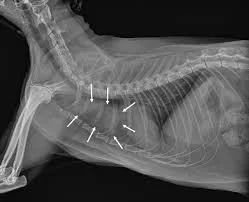

thymoma xray

Diagnosing thymoma usually involves several steps, because the tumor is located deep within the chest and may resemble other conditions.

Chest Radiographs (X‑rays)

X‑rays often reveal a mass in the cranial mediastinum. They may also show:

• Displacement of the trachea

• Fluid around the lungs

• Compression of lung lobes